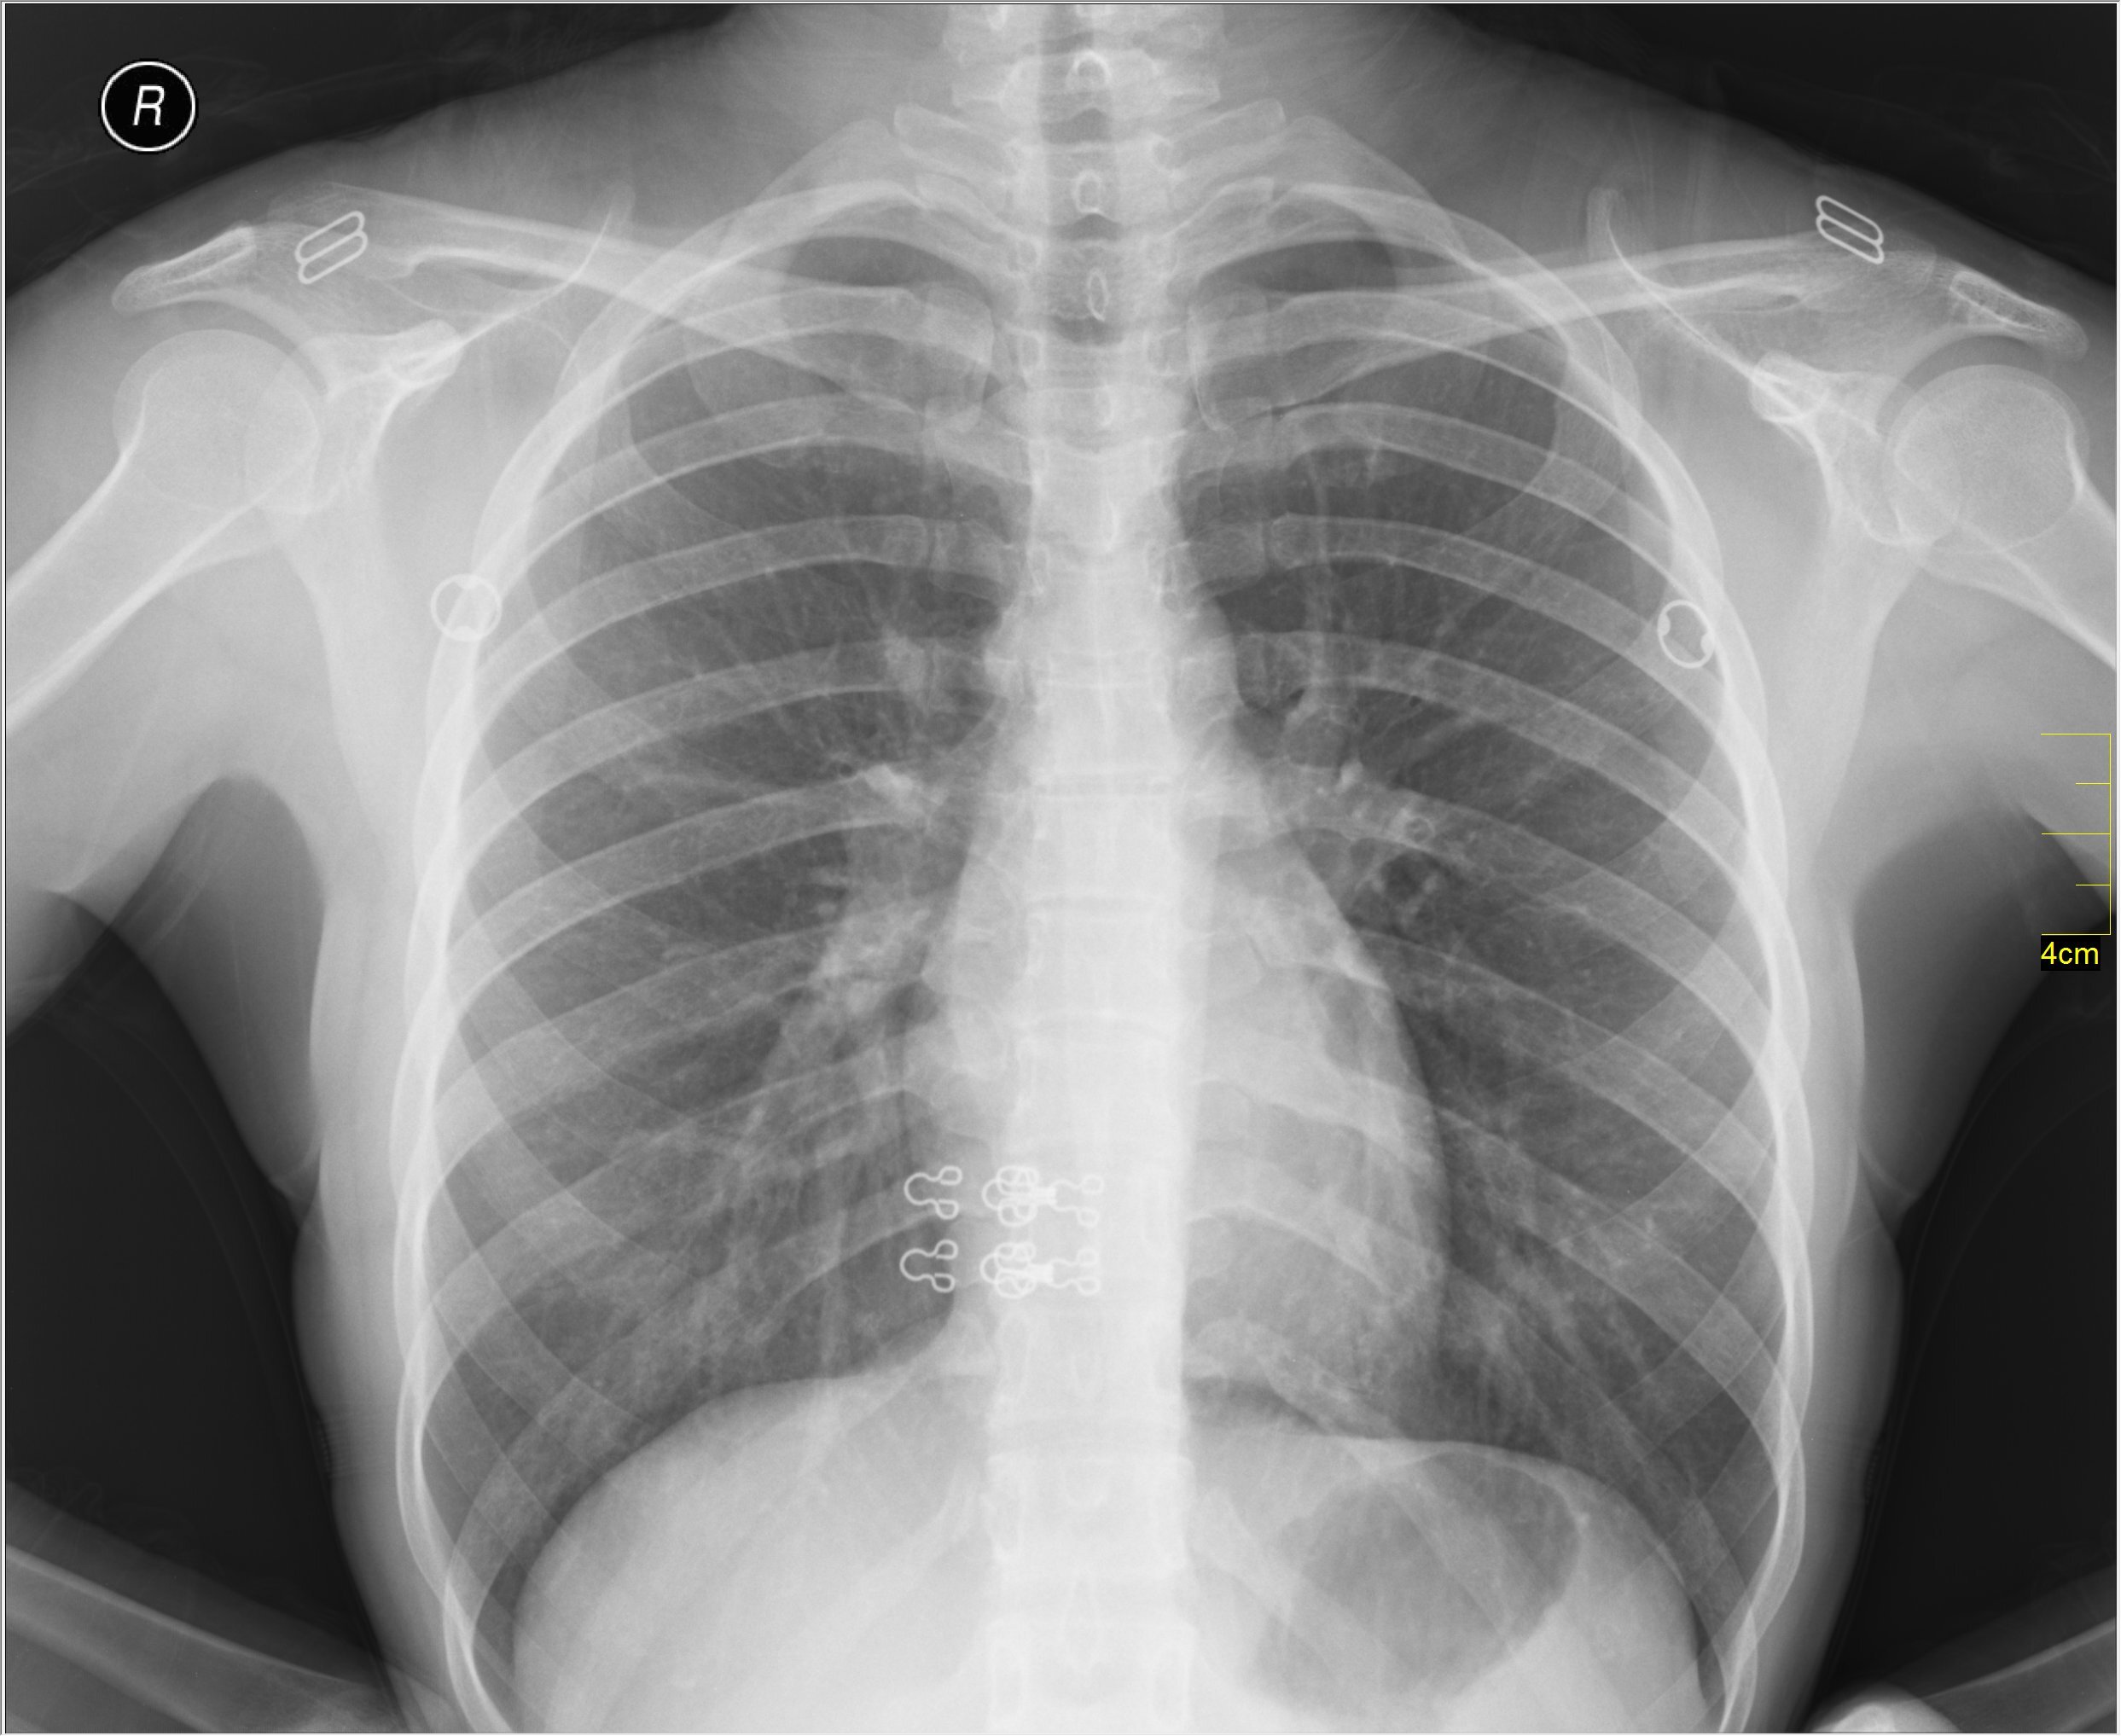

Для пневмонии характерно повышение температуры тела выше 39 градусов. В отличие от простуды патология вызывает боль в груди. Симптом может усиливаться при дыхании. Также пневмония вызывает кашель с мокротой, лихорадку, озноб, сильную потливость, одышку, спутанность сознания, хрипы.

Фото: commons.wikimedia.org, Nevit Dilmen (talk), Creative Commons Attribution-Share Alike 3.0 Unported license.